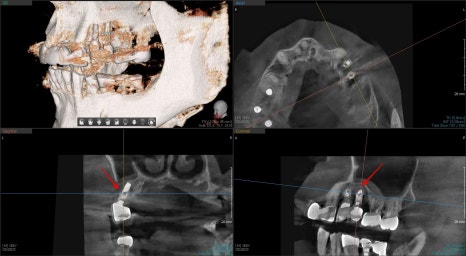

3D CT를 찍어봤더니 역시나 뿌리 주변의

심한 골소실로 인한 동요도로 인한 통증으로 진단하고

환자분께는 치아의 수명이 다해서 더 이상 치료는 불가능하고

발치 후 즉시 임플란트 수술에 대해 설명드렸습니다.

3D CT를 보면 역시나 임플란트가 주변 뼈에 의해

고정을 받고 있지 않았습니다.

치료상 임플란트는 쉽게 제거가 되었고 이미 뿌리 주변에

심한 오염이 진행되어 있었습니다.